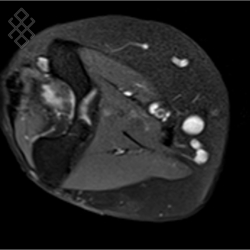

IRM du Coude

Vous entrez dans l'aimant, ouvert des 2 côtés, la tête la première et allongé sur le dos avec les bras le long du corps. Pour recueillir le signal et construire les images, vous aurez le coude dans une antenne. Étant donné que cet examen est bruyant, vous aurez à votre disposition des tampons auriculaires pour atténuer le bruit de la machine.